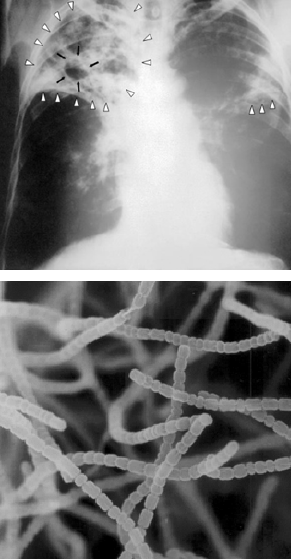

Image radiologique d’un poumon humain gravement infecté par Mycobacterium tuberculosis. Micrographie de Streptomyces griseus filamenteux. (En bas) : la largeur de chaque filament est d’environ 0.5 micromètre) ; la bactérie du sol qui produit la streptomycine, le premier antibiotique à vaincre efficacement M. tuberculosis.

L’équipe voulait en savoir plus sur la nature chimique complexe de l’humus d’un sol (voir le chap. 3), y compris le rôle que pouvaient exercer les microorganismes du sol dans la formation et la décomposition dudit humus. L’équipe de recherche de Waksman s’était particulièrement intéressé aux propriétés physiologiques des champignons et bactéries présentes dans les sols, sachant déjà que certains produisaient de puissants antibiotiques. L’étudiant au doctorat Albert Schatz, supervisé par le professeur Waksman, avait caractérisé la grande collection de cultures de Streptomyces dont les souches provenaient de sols et de composts locaux. Ces bactéries étaient déjà reconnues pour leur capacité à tuer l’agent pathogène Mycobacterium tuberculosis. L’apport de l’étudiant aura été d’éventuellement isoler la streptomycine, le premier antibiotique qui avait effectivement tué l’agent pathogène sans avoir aussi tué le patient ! L’histoire raconte que, selon Schatz, le professeur Waksman avait si peur de travailler avec les cultures de Mycobacterium contre lesquelles aucun remède n’existait à l’époque qu’il ne s’était jamais aventuré dans le laboratoire où Schatz manipulait la bactérie responsable de la tuberculose. Les deux chercheurs ont publié ensemble cette découverte de la streptomycine. La production commerciale de la streptomycine a permis de sauver d’innombrables vies. Cette découverte avait suscité la controverse ; Schatz avait été d’abord exclu de tout paiement de redevances sur les brevets. Le prix Nobel de physiologie ou de médecine de 1952 n’avait été seulement attribué qu’au professeur Waksman. Il avait été jugé que la tâche d’obtenir les cultures de bactéries du sol était plus méritoire que celle, plus routinière, de tester l’effet antibiotique des bactéries.